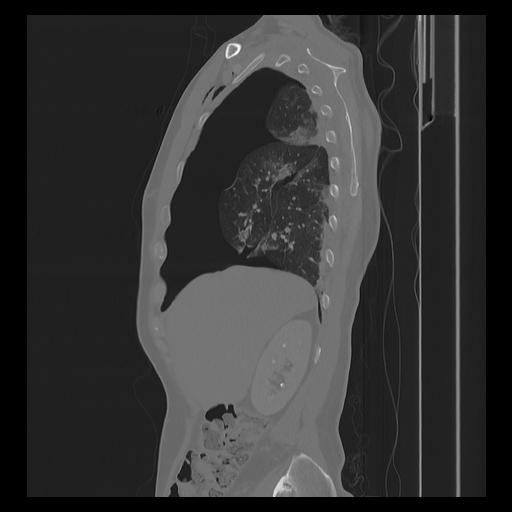

33 PULMON,CE,Sagittal,3.000,PULMON,Sagittal,